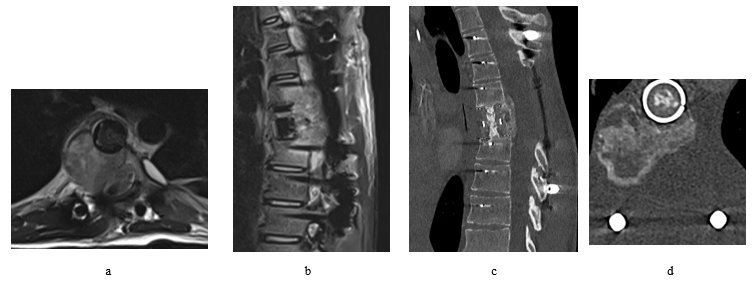

Figure 5: Despite all efforts fighting the tumor, follow up images shows recurrence of the tumor that aggressively invading the nearby structures. The MRI was performed 4 months after the second surgery (a + b). CT scans (c + d) were performed after the adjuvant radiation treatment, 7 months from the second surgery.

After 3 months of the surgery, follow up MRI scans were performed which had revealed recurrence of the tumor within the surgical bed with further bony destruction and epidural extension (Figure 4). The patient underwent T7 vertebrectomy followed by cage implantation then debulking of the residual tumor via left sided transthoracic approach. Patient has developed high fluid output per chest tube found to be due to CSF leakage which has been treated successfully conservatively, other than that, patient had made smooth recovery.

Follow up MRI and CT scans 4 months after the second surgery had revealed aggressive recurrence of the tumor invading nearby tissue and displacing the cord to the left (Figure 5). No metastatic deposits had been found so far on the follow up scans.

Adjuvant radiation therapy (50 Gray in 25 sessions) had been started after recovery and completed in mid-August/2023. Follow up post radiation CT scans showed continuing tumor growth.